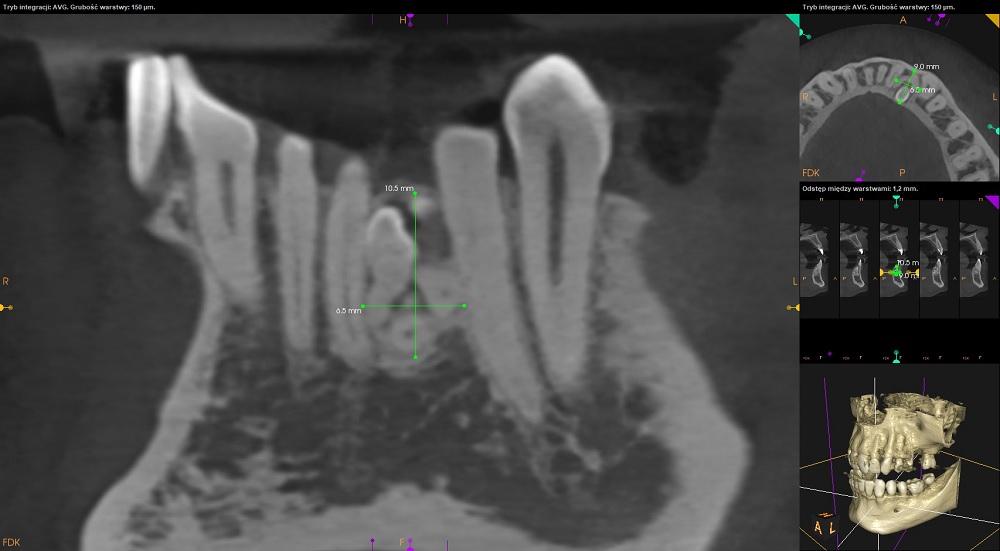

Na obrazie uzyskanym po wykonaniu tomografii CBCT pomiędzy korzeniami zębów 33 i 32 uwidoczniono owalny obszar otoczony rąbkiem przejaśnienia, wypełniony masą drobnych odontoidów (10,5mm x

9mm x 6,5mm).

Widoczna niewielka resorpcja korzenia zęba 32.